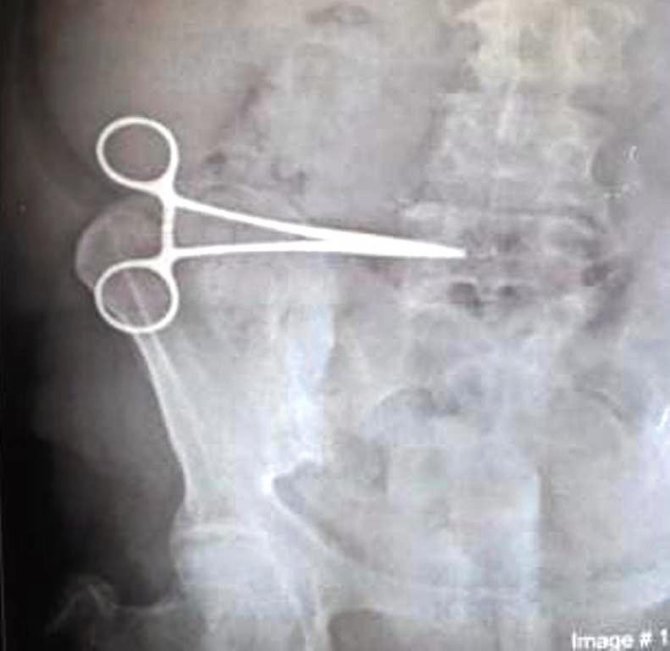

Aydın'ın Kuşadası ilçesinde yaşayan Nurcihan Öğmen'in (65), mide şikayeti nedeniyle özel bir hastanede geçirdiği operasyon sırasında karnında makas unutuldu. Ameliyattan sonra ağrıları dineceğine daha da artan Öğmen, daha sonra gittiği Söke Devlet Hastanesi'nde yapılan incelemede karnında makas unutulduğunu 2 ay sonra öğrendi. Özel hastanedeki ameliyat ekibinin Nurcihan Öğmen'in karnında unuttuğu makas Söke Devlet Hastanesi'nde yapılan ikinci bir ameliyatla alındı.

Edinilen bilgiye göre; Kuşadası'nda yaşayan Nurcihan Öğmen (65), 5 Mart 2021'de Kuşadası'ndaki özel bir hastanede mide rahatsızlığı nedeniyle operasyon geçirdi. Hastanede yapılan ameliyattan bir gün sonra taburcu edilen Öğmen'in ağrıları hiç dinmedi. Durumu doktoruna bildiren Öğmen buradan sonuç alamayınca 3 Mayıs 2021'de Söke Devlet Hastanesi'ne müracaat etti. Burada hastaya çekilen röntgeni inceleyen doktorlar gözlerine inanamadı. Hastanın 2 aydır karnında unutulan makas ile yaşadığını fark eden doktorlar Nurcihan Öğmen'i ameliyata alarak kadının karnında unutulan makası çıkardı.